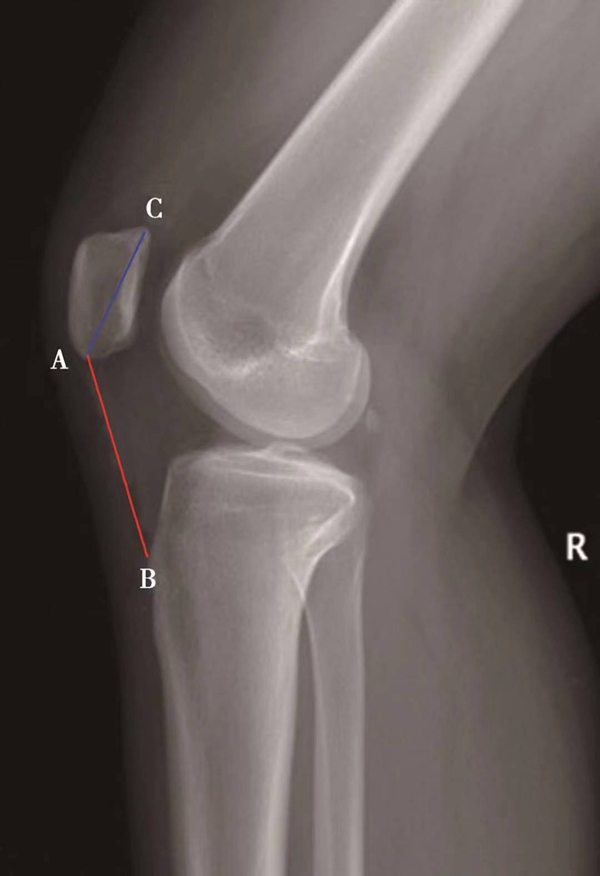

如图示:AB为髌骨关节面最低点到胫骨平台轮廓前上角最短的距离,AC是髌骨关节面的长度。Caton指数=AB/AC(图1)。

图1

图2 Caton指数=AB/AC=1.10,为正常髌骨高度

临床工作中常常使用其来估计胫骨结节移位的效果。正常人的Caton指数=1,正常范围0.8~1.2(图2)。需要注意的是:术前规划胫骨结节需要移位的理论距离为AB-AC,这就是需要将胫骨结节向远端移位的最大距离。但在术中胫骨结节转移的距离往往要小于这个距离,避免因过度移位造成医源性的低位髌骨。